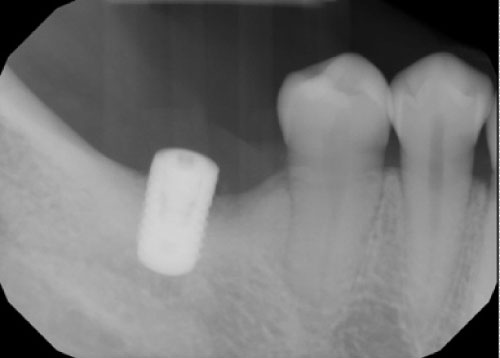

A 41-years-old patient presented with a restored dental implant in the mandibular posterior molar area, the implant fixture was placed approximately eight years ago and restored few months afterwards. The intra-oral exam revealed 5-6 mm pockets around the implant with slight inflammation of the surrounding soft tissue including bleeding upon probing and exudate. No mobility was detected and the patient was asymptomatic. The radiographic exam (Figure 1) revealed considerable bone loss with no other findings. The implant crown was removed and a cover screw placed. The Surgical treatment included a circumferential incision around the implant (Figure 2) followed by excavating the granulation tissue into the bony defect, scaling the implant surface using ultrasonic scalers and then using Prefgel to decontaminate the implant surface (Figure 3). A bone mix of mineralized cortico-cancellous allograft with Amnion-Chorion strips used to fill the bone defect (Figure 4 and Figure 5) and followed by mono filament non-resorbable suture (Figure 6). The patient placed on systemic antibiotics for one week and was prescribed chlorhexidine mouth wash in addition to mild analgesics. Two weeks post-operatively the patient presented with uneventful healing of the soft tissue and complete healing of the surgical wound over the bone graft mass (Figure 7). Three months following the procedure a periapical film showed considerable fill of the bone defect with integration to the implant surface (Figure 8).

Figure 1: Periapical film of the implant before treatment. View Figure 1